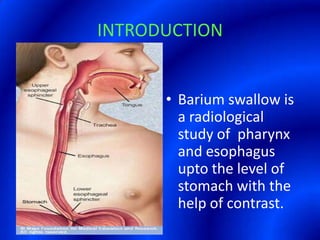

This document provides information about a barium swallow procedure. It begins with an introduction and overview of the embryology and anatomy of the pharynx and esophagus. It then describes the procedure itself, including preparation, technique, views obtained, and indications. Specific conditions that may be examined include pharyngeal and esophageal webs, foreign body impaction, scleroderma, dysphagia, mediastinal masses, and carcinoma. Diagrams are provided to illustrate normal anatomy and various pathological findings.